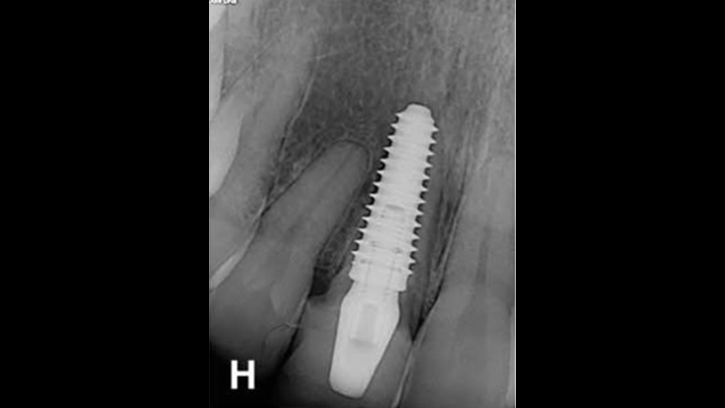

“AnyRidge implant enables fast and stable

osseointegration at this extreme case of bone defect. ”

Clinical case: Bone filling into the bottom of deepest thread at 8.0mm AnyRidge fixture

- Courtesy of Dr. Kwang Bum Park -

AnyRidge, Knifethread ,extraction socket, ,initial stability ,Allograft, ,osseointegratio ,Dr. Kwang Bum Park, , Mandibular, Single replacement, AnyRidge, Mega-oss,

Implant system-AnyRidge, Regeneration-Mega-Oss

How can primary stability be increased?

Primary stability is especially important in the case of poor quality bone. The instability of dental implants results in fibrous encapsulation and failed osseointegration (Lioubavina-Hack, et al. 2006). One method for increasing primary stability is modifying the surgical technique for implant placement. Studies have reported that the undersized surgical technique, which uses a final drill diameter smaller than the diameter of the implant, results in a higher primary stability when compared with the press-fit technique (Tabassum, et al. 2009, Tabassum, et al. 2010a).

Ti implants with a deeper thread depth provide a higher surface area, which is advantageous for increasing stability in areas of poor quality bone (Abuhussein, et al. 2010). Ti implants with deeper thread depths also facilitate an increased load and mechanical interlocking with poor quality bone.

Another method increasing the primary stability is to change the implant design, such as the shape of the implant body and thread, length, and diameter. Various thread designs for taper implants and other dental implant designs have already been reported to effect the primary stability. Taper implants also show a higher primary stability than cylindrical implants (Kim, et al. 2009, Sakoh, et al. 2006, Wilmes, et al. 2008).

Meanwhile, dental implants with a long length or wide diameter show a significantly increased insertion torque (Kim,et al. 2009, Wilmes, et al. 2008). Plus, dental implants without self-tapping blades have a higher primary stability than implants with self-tapping blades (Kim et al. 2011).